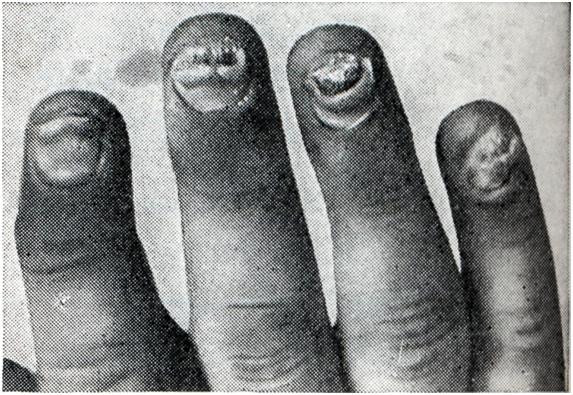

Псориатический полиартрит (polyarthritis psoriatica) развивается чаще у больных, уже имеющих кожные проявления псориаза, в среднем через 6 лет после их появления, но иногда может им предшествовать или появиться одновременно. Псориатический полиартрит в наст, время выделен в самостоятельную нозологическую форму. Клиническая картина его чрезвычайно похожа на ревматоидный артрит, однако имеет некоторые особенности: 1. Почти всегда поражаются дистальные межфаланговые суставы пальцев рук. Одновременно, как правило, поражаются ногти (рис. 18). 2. В процесс вовлекается обычно небольшое количество других периферических суставов (2—3, редко больше), при этом поражение носит асимметричный характер. В тяжелых случаях суставной процесс может быть генерализованным. 3. Поражаются межпозвонковые суставы поясничной области и крестцово-подвздошные суставы, где могут развиваться анкилозы, поэтому псориатический полиартрит нужно дифференцировать с болезнью Бехтерева. 4. Течение обычно ремиттирующее, резкие обострения часто чередуются с частичными ремиссиями. При этом отмечается определенный параллелизм с кожными проявлениями псориаза.

Рис. 18. | ||

На рентгенограмме кистей часто обнаруживается лизис дистальных фаланг пальцев (мутилирующий артрит), что характерно и для склеродермии. В остальном рентгенологическая картина мало отличается от картины при ревматоидном артрите.

Реакция Валера — Роуза и проба с латексом или дерматолом (смотри Ревматоидный артрит), как правило, отрицательные. Лабораторные данные показывают сдвиги, характерные для воспалительного процесса (ускорение РОЭ, лейкоцитоз, гипер-гаммаглобулинемия).